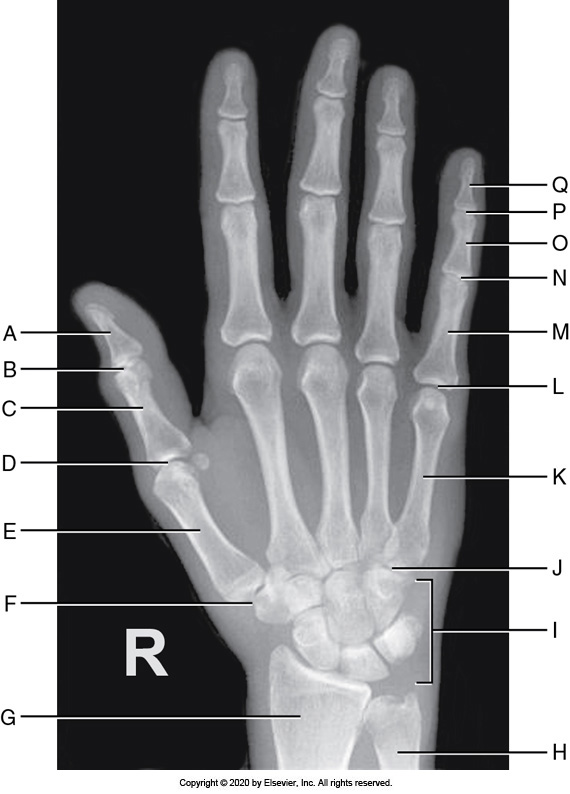

Identify the labeled "B" anatomy below:

Interphalangeal joint

Identify the labeled "G" anatomy in the image below:

Trapezium